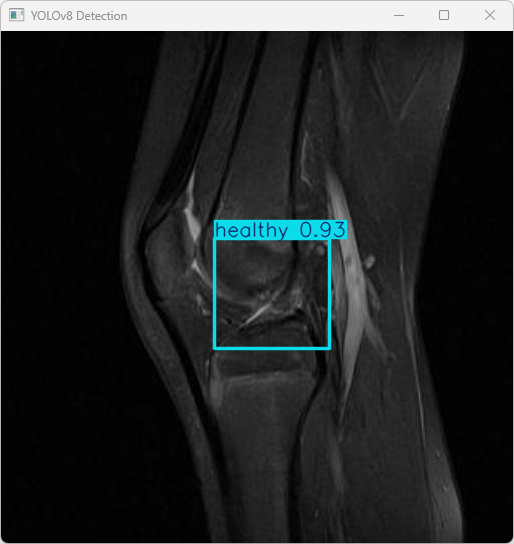

此代码的功能是加载一个预训练的YOLOv8模型,对指定的图片进行目标检测,并将检测结果显示出来。

执行imgTest.py代码后,会将执行的结果直接标注在图片上,结果如下:

这段输出是基于YOLOv8模型对图片“imagetest.jpg”进行检测的结果,具体内容如下:

图像信息:

(1)处理的图像路径为:TestFiles/imagetest.jpg。

(2)图像尺寸为 610×640像素。

检测结果:

(1)检测到1个“healthy”(健康)的膝关节状态。

处理速度:

(1)预处理时间: 4.1 毫秒

(2)推理时间: 4.7 毫秒

(3)后处理时间: 68.5 毫秒

模型成功检测出膝关节状态为“健康”,处理速度较快。可以通过读取boxes对象来获取检测框的详细信息,例如坐标和置信度等。